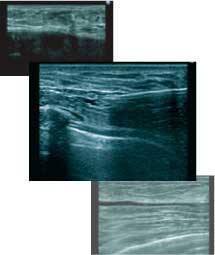

そのため、THE CLINICでは最先端のエコーである「エラストグラフィー」を導入し、正確に目視しながら溶解注射を行っています。

大量のしこりがあった場合など、術後、本当に除去できたのか気になる方もいらっしゃると思います。そこで当院では、希望される方に術前・術中・術後のエコー画像を用いてご説明し、完全にしこりがなくなったことをご自身でも確認できるように配慮しています。